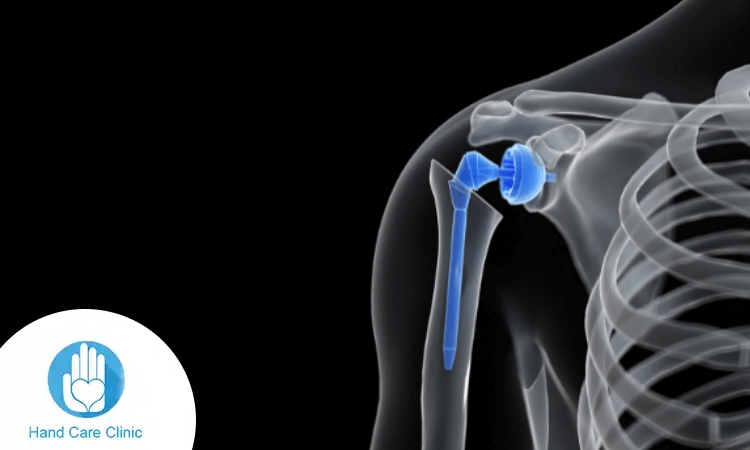

استبدال المفصل

يُجرى في الحالات المتقدمة من الخشونة.